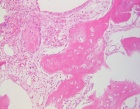

R.H. - 66 year old male presents with LBP for several months. No complaints of hip pain.

Zoom image: Cell stain Cell stain.